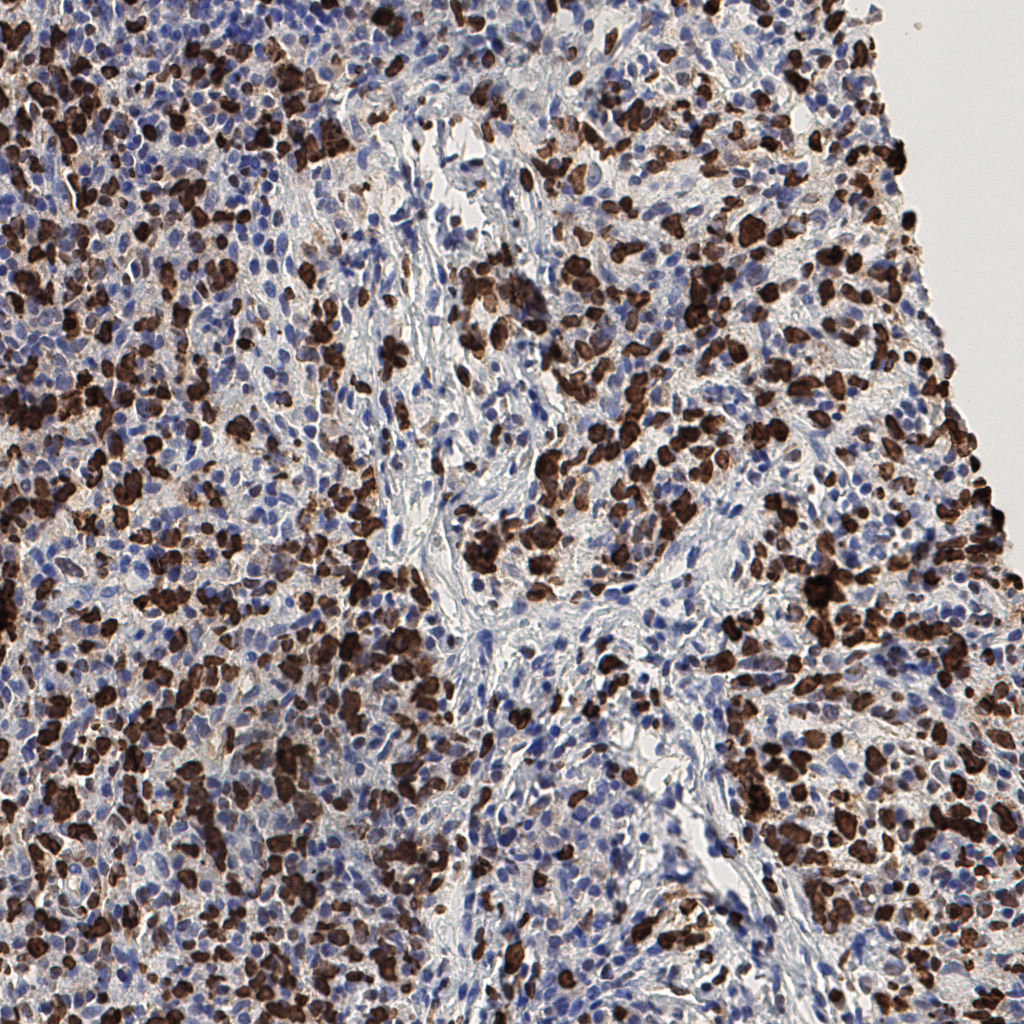

7.85%

Ki67 指数

阴 1104 阳 94

H255858-KI-67.ndpi